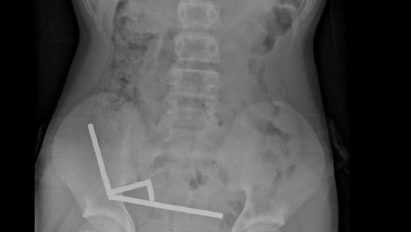

Os exames de imagem, incluindo tomografias e radiografias abdominais, revelaram o cenário crítico: os ímãs haviam se agrupado em quatro correntes dentro do abdômen, conectando diferentes partes do intestino entre si. Essa ligação magnética criou uma espécie de “anel de pressão” que, ao longo dos dias, começou a destruir o tecido intestinal.

Diante da gravidade do caso, os médicos decidiram realizar uma cirurgia de emergência. Durante o procedimento, conseguiram remover os ímãs — todos concentrados em blocos fortemente aderidos. No entanto, parte significativa do intestino precisou ser retirada, devido à necrose causada pela compressão.